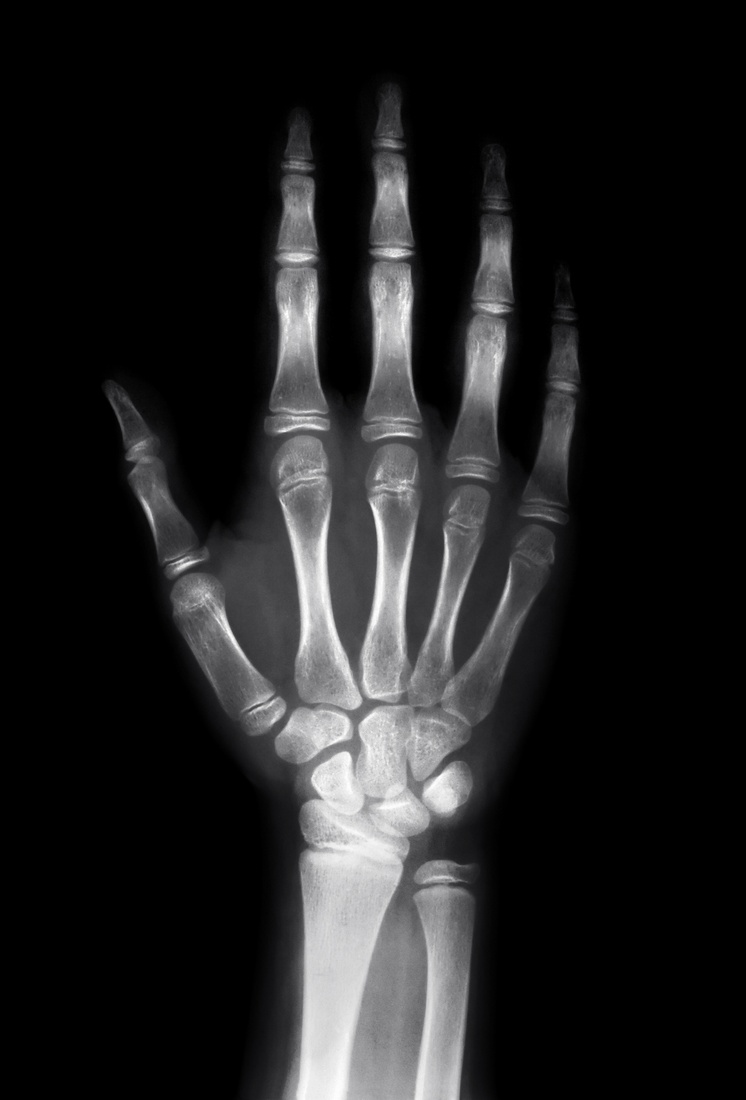

Sulla salute la prudenza non è mai troppa, salvo evitare la cattiva informazione e i luoghi comuni. Bene dunque cautelarsi e prendere sul serio i consigli circa i possibili rischi. Ma bene anche valutare la loro fonte e sostanza scientifica. Ebbene, da un’equipe di ricercatori americani sembra emergere che i timori circa l’effetto cancerogeno dei raggi X siano del tutto privi di tale base.

Lo sforzo degli oncologi del Loyola University Medical Center, alle porte di Chicago, è stato quello di una revisione sistematica dell’intera letteratura scientifica in materia negli ultimi 70 anni, ossia dall’orrore dei bombardamenti atomici. La conclusione è che le preoccupazioni di alcuni pazienti (e pochi medici) dinanzi a una radiografia o una Tac si basano su “ipotesi solo teoriche, che non hanno mai trovato il riscontro di alcuna prova”. Alla conclusione segue un alert, quello sulle “spese eccessive per misure di sicurezza azzardate quanto inutili e costose”.